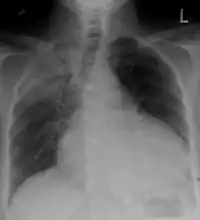

Chest X-ray showing a massive pericardial effusion: Water bottle sign

Chest x-ray: is non-specific and may not help identify a pericardial effusion but a very large, chronic effusion can present as "water-bottle sign" on an x-ray, which occurs when the cardiopericardial silhouette is enlarged and assumes the shape of a flask or water bottle.[2] Chest radiograph is also helpful in ruling out pneumothorax, pneumonia, and esophageal rupture.